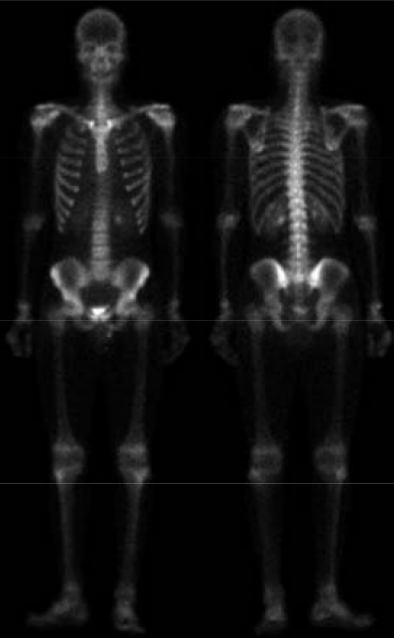

| Kindulási kép: | Ez lett belőle: |